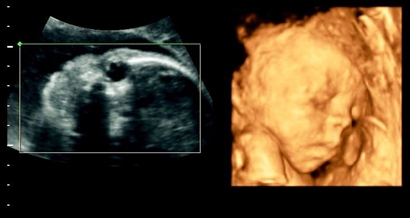

四维看是男孩有可能是女孩吗,四维男翻女的几率多大?

四维彩超是实时的立体成像,在孕检的时候主要是帮助筛查胎儿的畸形,四维由于清晰度高也有用来判断胎儿男女,那么四维看是男孩有可能是女孩吗,四维男翻女的几率多大?四维..